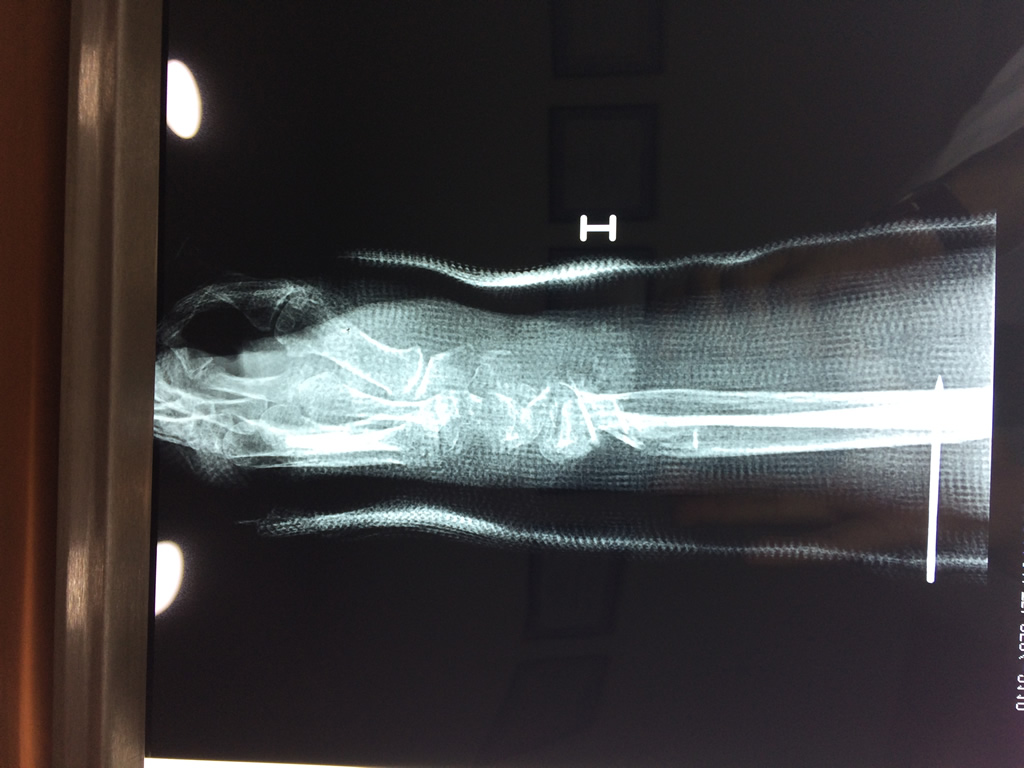

Calcaneo - Cirugías de Muñecas y Manos

Los procedimientos más comunes en cirugía de la mano son aquellos destinados a reparar traumatismos, incluyendo lesiones de tendones, nervios, vasos sanguíneos, y articulaciones; huesos fracturados; y quemaduras, cortes, y otros daños de la piel.